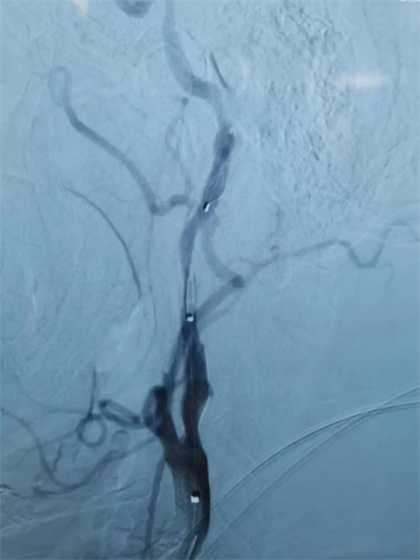

颈内动脉起始部是动脉粥样硬化性斑块容易形成的部位,如果没有及时发现和治疗,斑块逐渐增大造成颈内动脉狭窄,更为严重者颈内动脉完全闭塞,导致同侧大脑半球大面积梗死。近日我院神经内科成功为一名颈内动脉次全闭塞患者实施血管内治疗,保全了病人的颈内动脉,避免了脑梗死进一步加重。

患者 刘某某,男性 68岁,因“急性脑梗死”在我院神经内科住院治疗,入院头颅CTA、CTP检查发现,病人左侧颈内动脉起始部接近闭塞,只有线样血流,同侧大脑半球大片低灌注区。入院后经强化的药物治疗,患者的症状仍有波动,时常出现言语不清、肢体无力加重等症状。神经内科科内讨论认为:病人的左侧颈内动脉起始部极重度的狭窄,同侧颅内血流动力学不稳定,如果不采取有效的措施,患者的颈内动脉有随时完全闭塞的风险,脑梗死会进一步加重,从而导致严重的失语、偏瘫症状,那对病人及其家庭将是一场灾难。经与患者家属沟通后,于3月4日上午,神经内科介入团队盛守权主任、张国柱副主任医师成功为患者实施颈动脉球囊扩张和支架置入手术,术后病人颅内供血立即改善,症状波动消失,现已经康复出院。